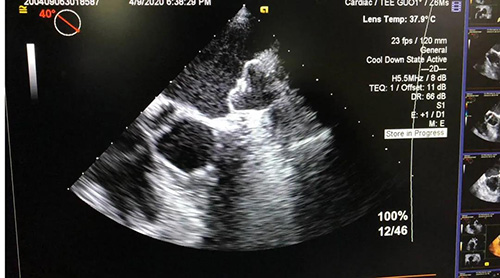

4月9日,山东第一医科大学附属省立医院(山东省立医院)成功举办房颤左心耳封堵手术直播线上演示会。心内科主任医师朱贵月成功实施一例房颤左心耳封堵手术,其首创的RAO 35º+上腔静脉造影指引下房间隔穿刺术,获得业内高度关注。

本次手术通过网络全程直播,从股静脉穿刺、房间隔穿刺、左心耳造影、选择合适封堵器到左心耳完美封堵,手术的每一步关键细节都得到详细讲解,精准解答,并与省内外专家进行线上讨论。直播手术吸引了6000余名专业人士同时在线观看。

房间隔穿刺术是左心耳封堵的关键环节,心脏电生理医师常规选用传统RAO 45º作为穿刺体位,朱贵月主任医师阅读国内外大量关于房间隔倾斜角度的文献资料,结合临床介入操作实践,首创RAO 35º+上腔静脉造影指引下房间隔穿刺术,既提高穿刺位点的准确性,又保证手术的安全性,使介入医师大大缩短了手术学习曲线。